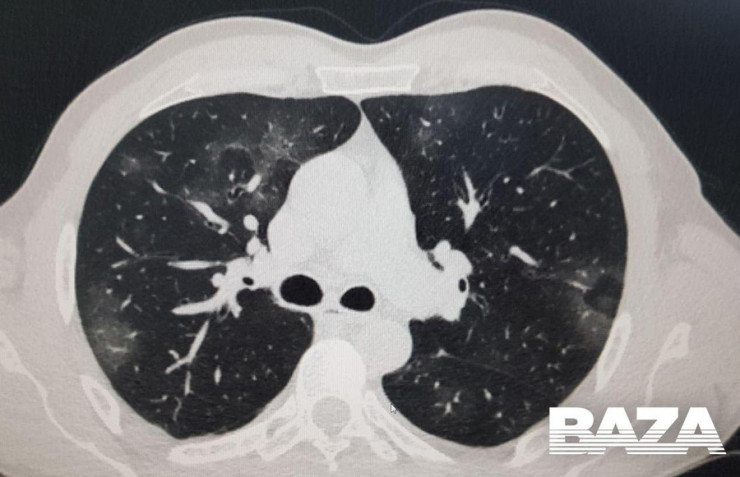

Одна из отличительных особенностей вирусной пневмонии - это симметричное поражение легких с полисегментарными воспалительными изменениями (в нескольких частях, то есть в разных долях и разных не смежных сегментах). Другие виды пневмонии развиваются, как правило, в пределах одной доли легкого, а не везде. Так, при заболевании COVID-19 на компьютерных томограммах видны уплотнения легочной ткани, похожие на прозрачные потертые пятна. В медицине такие патологии называют симптомом "матового стекла".

На ранней стадии развития вирусной пневмонии (проявляется до четвертого дня заболевания) "матовое стекло" возникает не более чем в трех очагах. При этом уплотнения распространяются преимущественно в нижних долях и по периферии, а их максимальный диаметр не превышает три сантиметра. Из-за повреждений в альвеолах скапливается жидкость, которая приводит к нарушению кислородного обмена и кислородному голоданию пациента, такие пациенты начинают жаловаться на одышку и затрудненность дыхания.